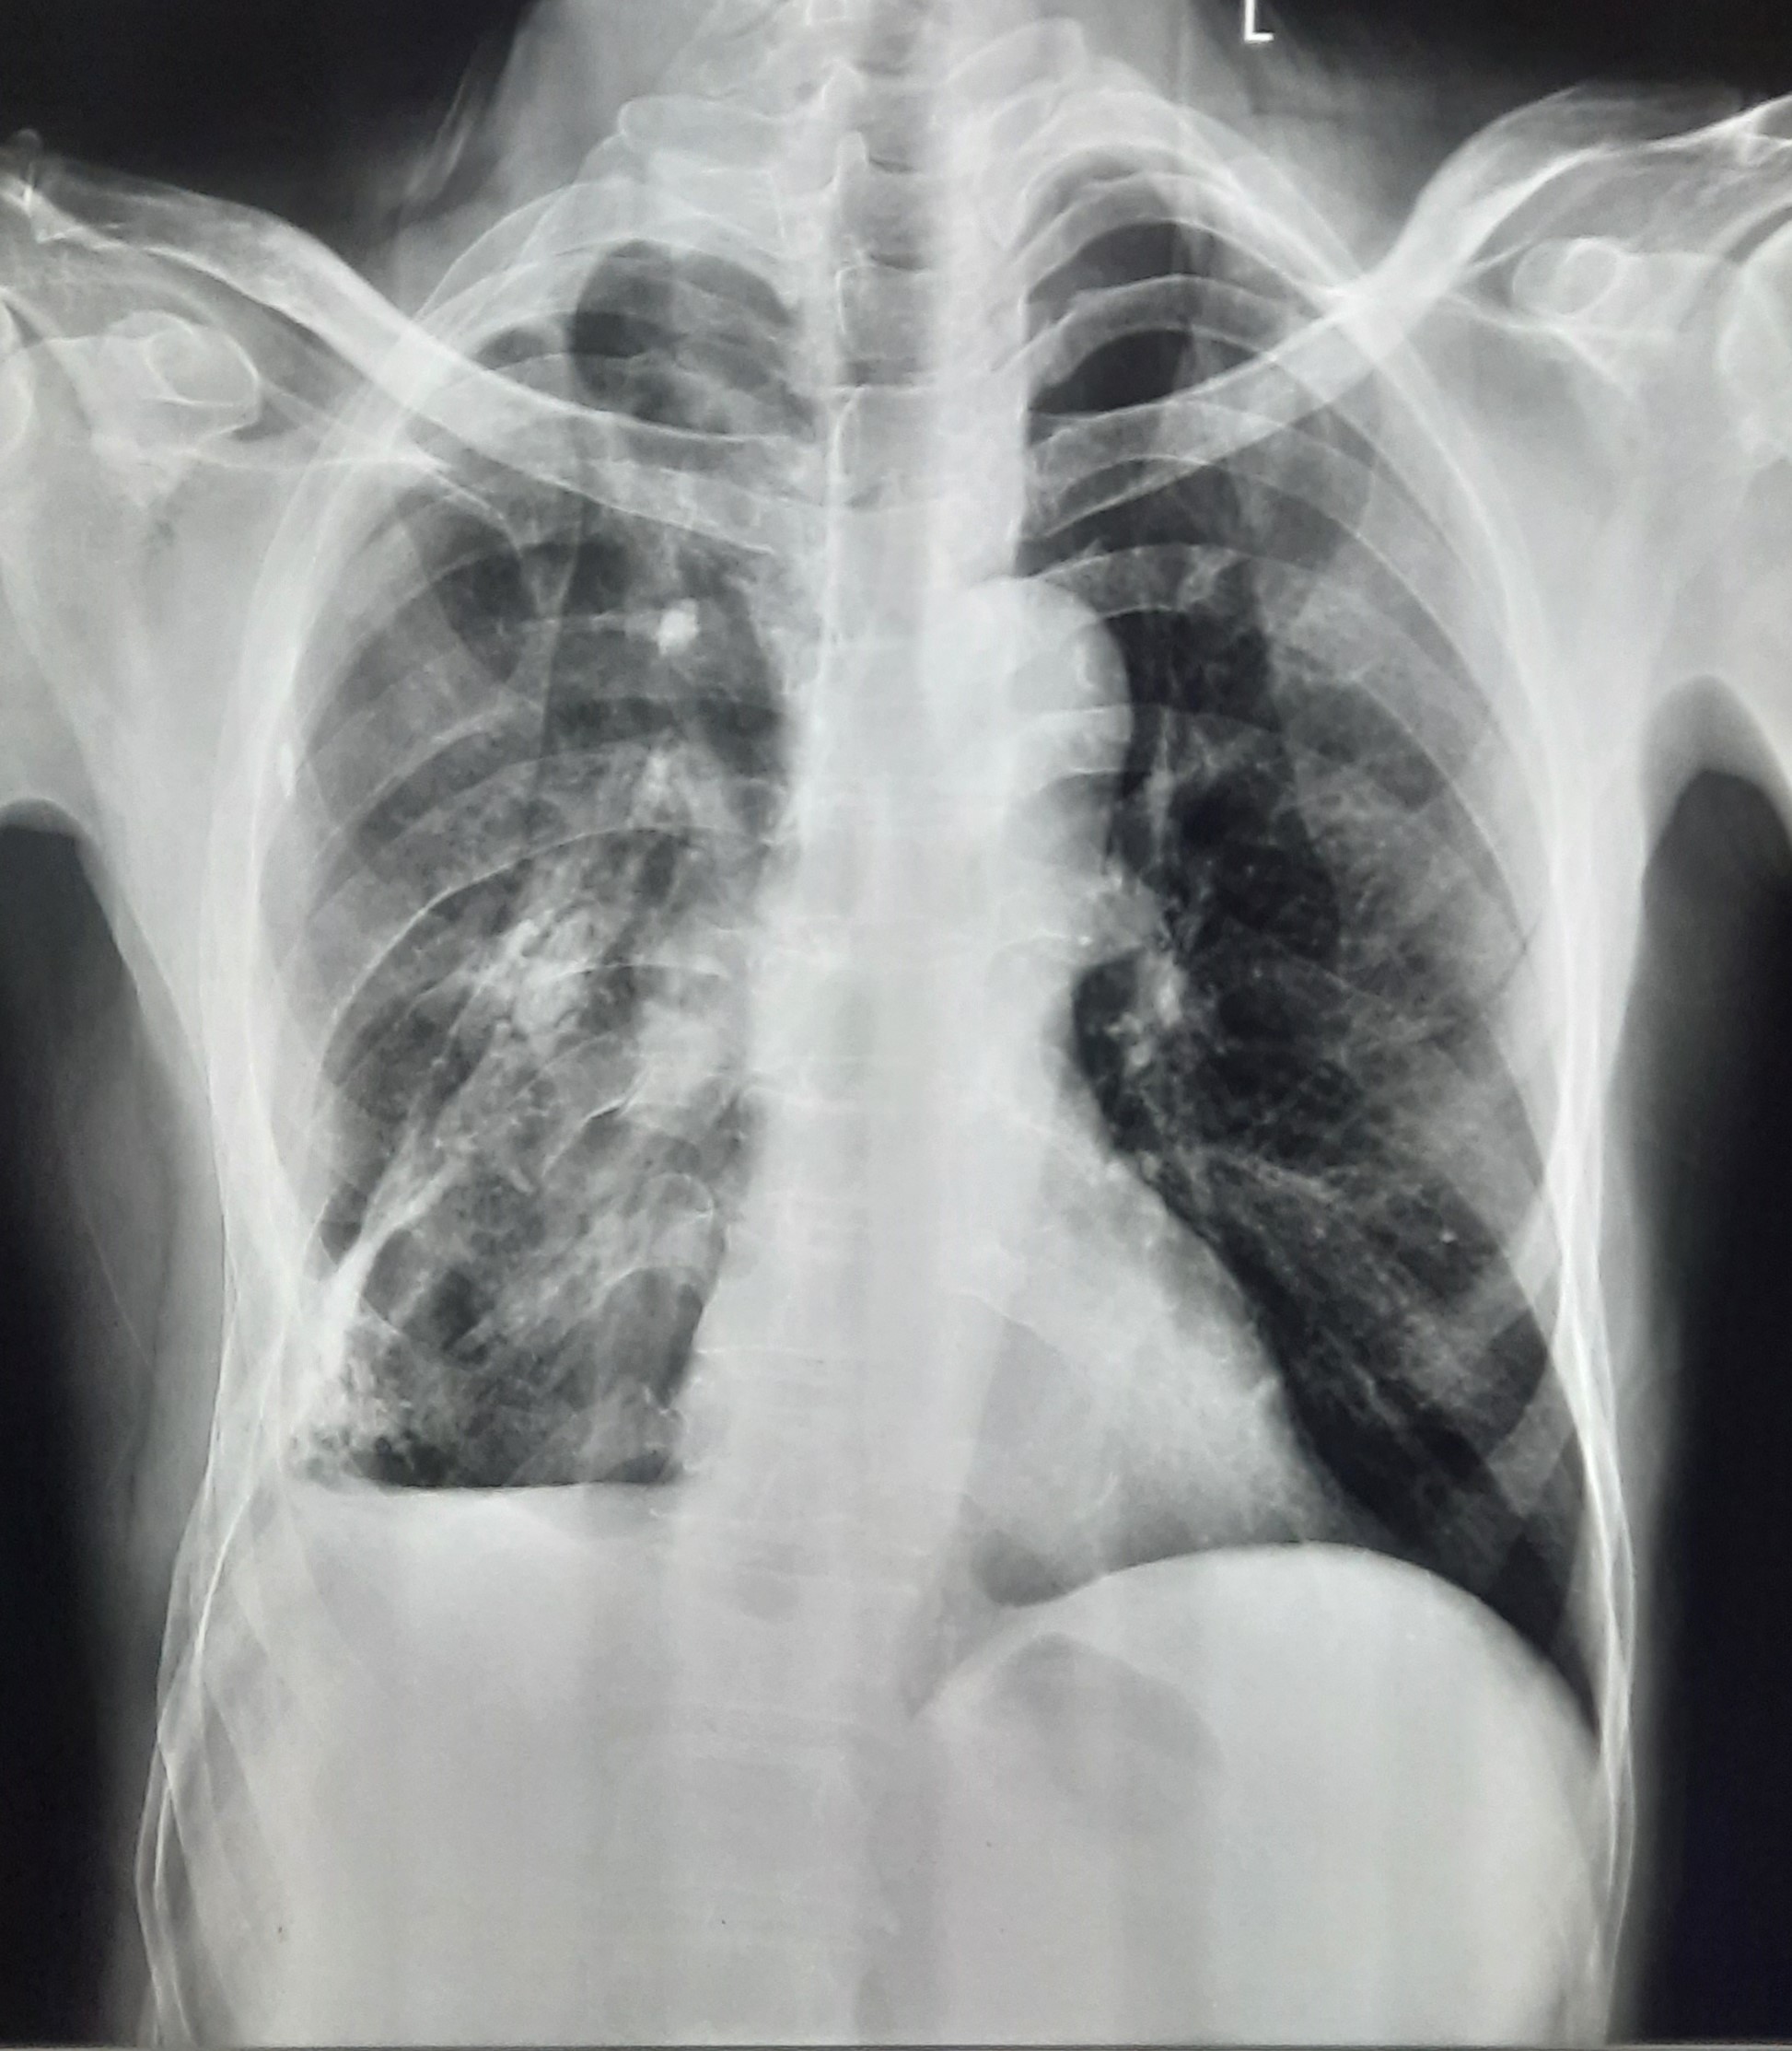

| 52 | IGGMC, Nagpur, Nagpur | P2 | 29-4420 | Hamida Bano | Consent taken on Paper | 56 Yrs. |

Provisional Diag : Post TB Sequelae With Reactivation?

Final Diag : Post TB Sequelae |

Post TB Sequelae | Tracheal Pull Left Side, Left Mid Zone & Upper Zone Fibro cavitary Lesion Present, Compensatory Right lung Hyper Infiltration Present, Few ill-defined Bilateral Lung Opacity Presnt | Abnormality visible on x-ray |